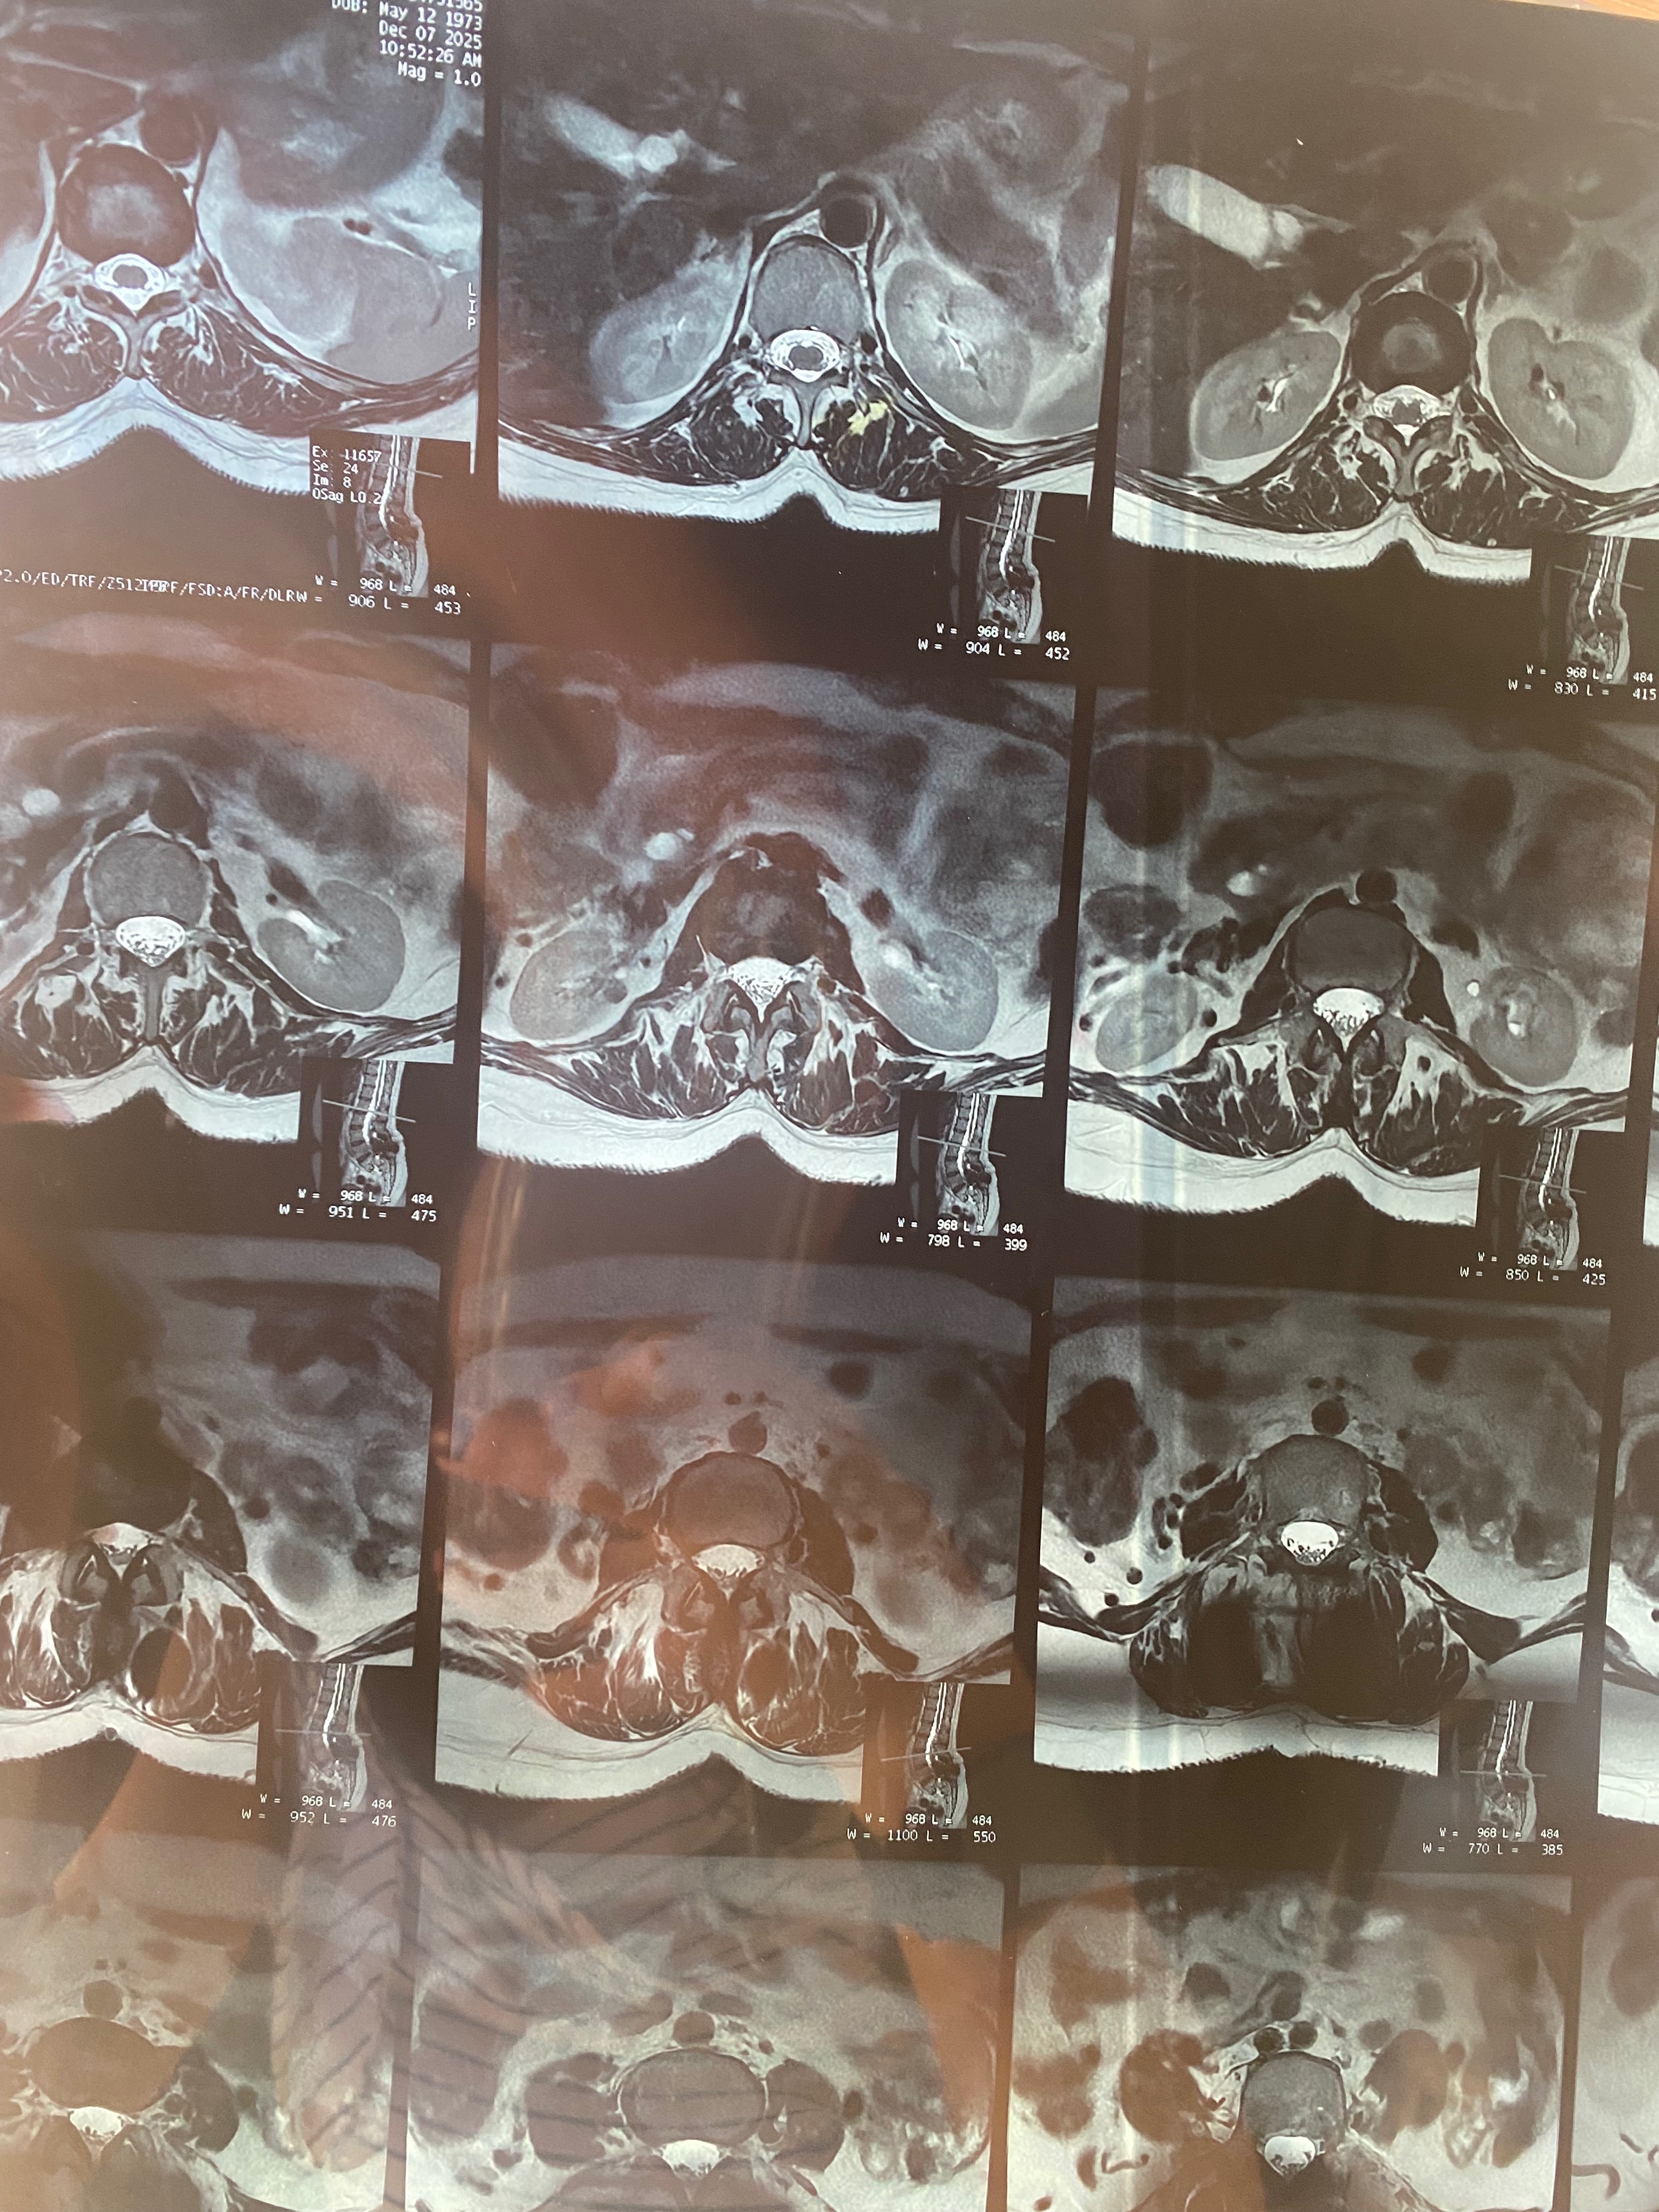

Hace 28 años, mi mamá fue operada de la columna y le colocaron prótesis de metal que, con el paso del tiempo, dejaron de ser funcionales. En los últimos meses, su condición ha empeorado: presenta dolor constante, adormecimiento en las piernas, mareos y una dificultad cada vez mayor para caminar, sentarse y descansar.

Buscamos atención en el sistema de salud público, pero nos informaron que no cuentan con el material necesario ni realizan este tipo de cirugía. Los médicos fueron claros: la intervención no es opcional. Si no se realiza a tiempo, mi mamá corre el riesgo de perder la capacidad de caminar.